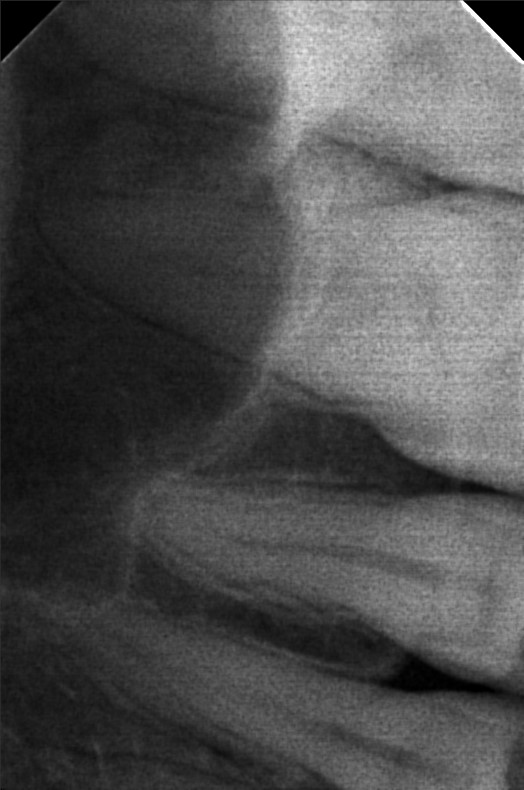

Edit Record Check our patient data records. Add patient information Patient Info Profile picture Last Name First Name Middle Name Birthdate Age Street Barangay City Country Zip Code Contact number Email Procedure 06/30/23- Informed Consent Ortho Check Up OP Impression Soft tissue analysis Intraoral photograph PA Radiograph For exo #15 Informed pt regarding class 5 cases Referred for cephalometric radiograph For resto class 5 #23, #24, #25, #35, #13, #14 10/24/25 oral prophylaxis xray tooth extraction #15 for restoration: abrasion: #23, 24, 25, 26, 14, 33, 35, 36, 44 recession: #13, 12, 11, 21, 22, 34, 32, 43 File atecotech2i712f_f.jpeg File 2 atecotech2i18f6_f.jpeg File 3 atecotech2i2a08_f.jpeg File 4 atecotech2i6330_f.jpeg File 5 atecotech2i278f_f.jpeg File 6 atecotech2i5dba_f.jpeg File 7 File 8 File 9 File 10 File 11 File 12 File 13 File 14 File 15 File 16 File 17 File 18 File 19 File 20 Retain Record Retain Record Yes No Save Your Changes